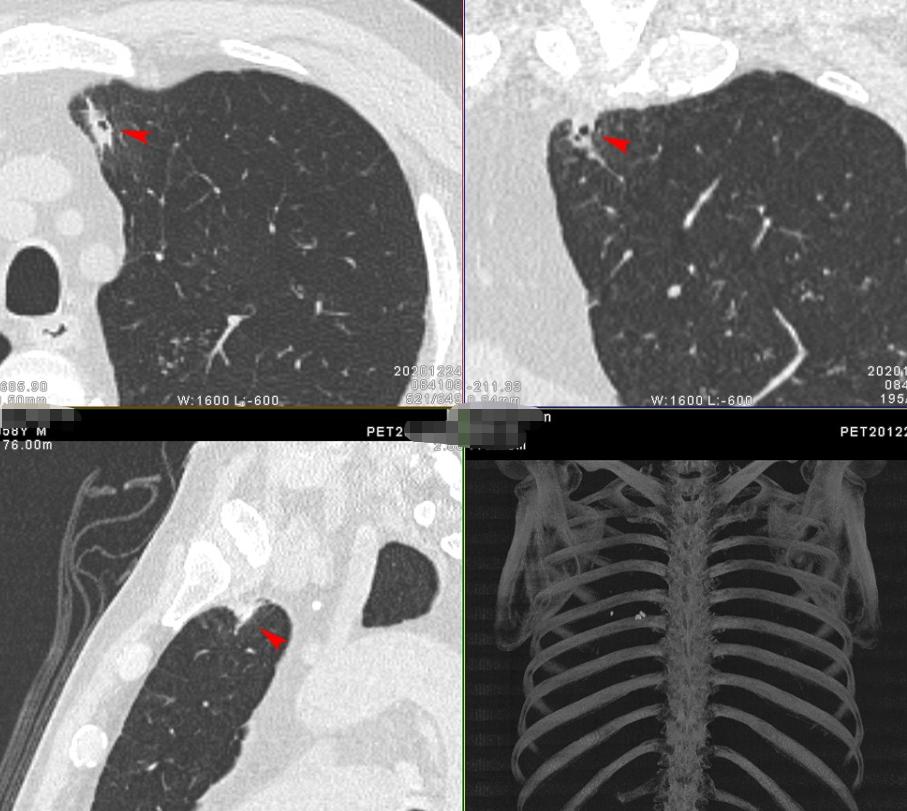

3. 男性 56岁 咳痰喘1月余。

这个就说怕不怕?结合全身状况,一锤定音,考虑为良性感染性病变,建议观察。

支气管镜活检:发现碳末沉积,未见癌细胞。

结合有灰尘接触史,考虑为尘肺合并陈旧性肺结核。目前8个月随访无明显变化。